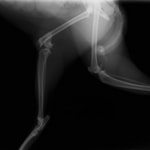

術前レントゲン